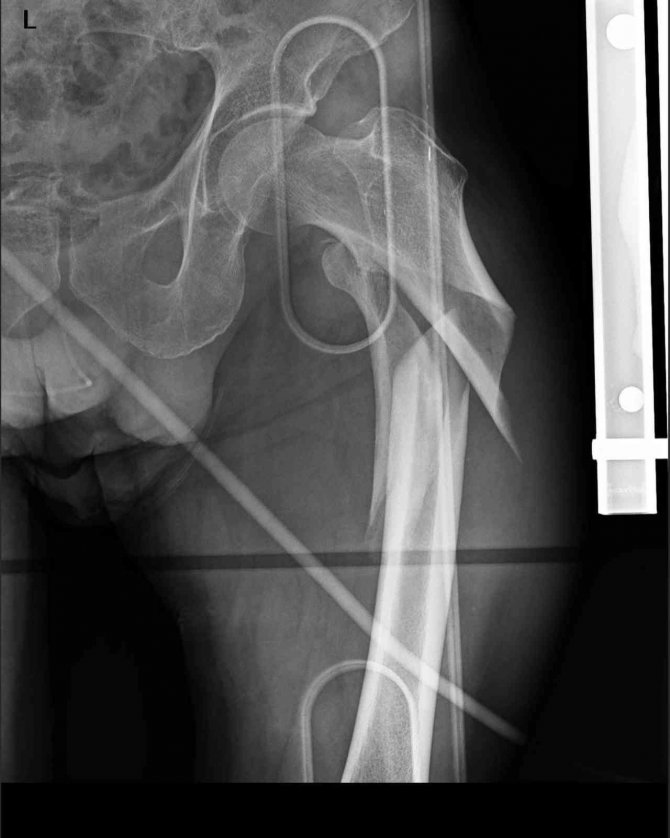

Düzce Üniversitesi Hastanesi Ortopedi ve Travmatoloji Kliniği'nde yaşlılıkta travmalara bağlı gelişen kalça kırıklarına yönelik yapılan başarılı operasyonlar hastaları yatağa bağlı kalmaktan kurtarıyor.

Yaşlılarda görülen kalça kırıklarının son derece önemli ve hayati kırıklar olduğunu ifade eden Düzce Üniversitesi Hastanesi Ortopedi ve Travmatoloji Anabilim Dalı Öğretim Üyesi Doç. Dr. Zekeriya Okan Karaduman, yaşlılığa bağlı kemik erimesi sonucu basit düşmelerde kalça kırığının sıkça görüldüğüne işaret etti. Riskli grupta olan geriatrik hastalarda kırığa erken müdahale edilmemesinin hayati riskler taşıdığını ifade eden Doç. Dr. Karaduman, hastanın yaşamına sağlıklı bir biçimde devam edebilmesi için kalça kırığının vakit kaybedilmeden alanında uzman ortopedi hekimi tarafından muayene edilmesi gerektiğini vurguladı.

Ortopedi ve Travmatoloji Anabilim Dalı Öğretim Üyeleri Doç. Dr. Yalçın Turhan ve Doç. Dr. Mehmet Arıcan'ın başında bulunduğu sağlık ekibiyle hastaların sağlık durumunu değerlendirerek en uygun tedavi yöntemine karar verdiklerini kaydeden Karaduman, hastaya özgü belirledikleri tedavi protokolüyle hastaların kısa sürede ayağa kalkarak normal yaşantısına dönmesini amaçladıklarını ifade etti.